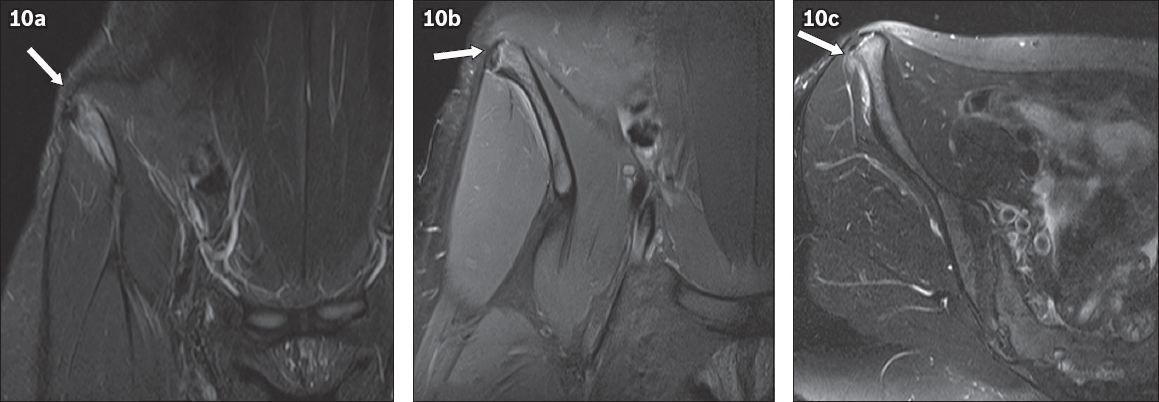

Fig. 10

(a) Coronal T2-W turbo inversion recovery magnitude; (b) coronal FS proton density; and (c) axial T2-W FS pelvic MR images of our index patient’s 15-year-old elder sister, who presented with a two-month history of right hip pain following regular running, show high signal at the right iliac crest apophysis. There is mild widening of the iliac crest apophysis, with no significant displacement (arrows). Mild oedema is noted in the adjacent right gluteus and lateral abdominal muscles.